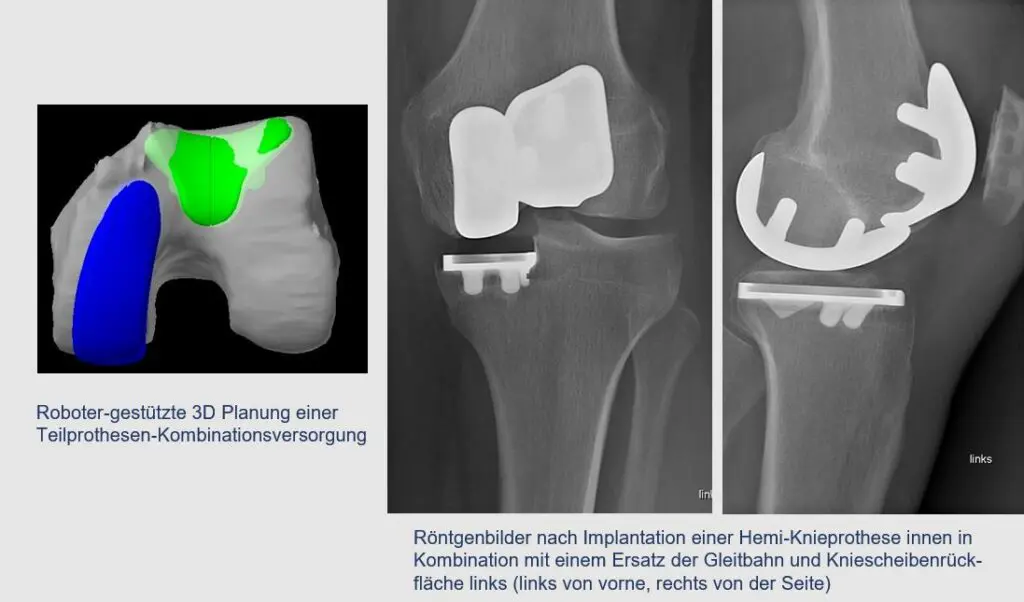

If more than one joint section is affected but the cruciate ligaments are still intact, various partial prostheses can also be combined with each other.

In our imagination, the knee joint consists of three compartments: Internal, external and the patellofemoral joint. In this concept of combination therapy, the surface of the affected joint sections is selectively replaced – depending on the individual situation. As already explained, in contrast to a total prosthesis, which replaces all three joint sections with one implant, both cruciate ligaments of the knee joint can be preserved. As a result, the natural range of motion is better preserved and the knee retains its original stability and proprioception, which leads to a more normal joint sensation. In addition, this procedure can be regarded as bone-sparing. The basic prerequisite for this type of treatment is intact ligament stability.

As the precise implantation and coordination of the individual prosthetic components in combined partial prosthetics is technically very demanding, we currently always offer this in combination with MAKO robot technology. This guarantees the precise individual positioning of the implants in the bone.